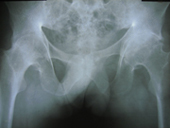

Arthriis of both hips pre op Arthriis of both hips post op Arthritis knee valgus deformity pre op Arthritis knee valgus deformity post op